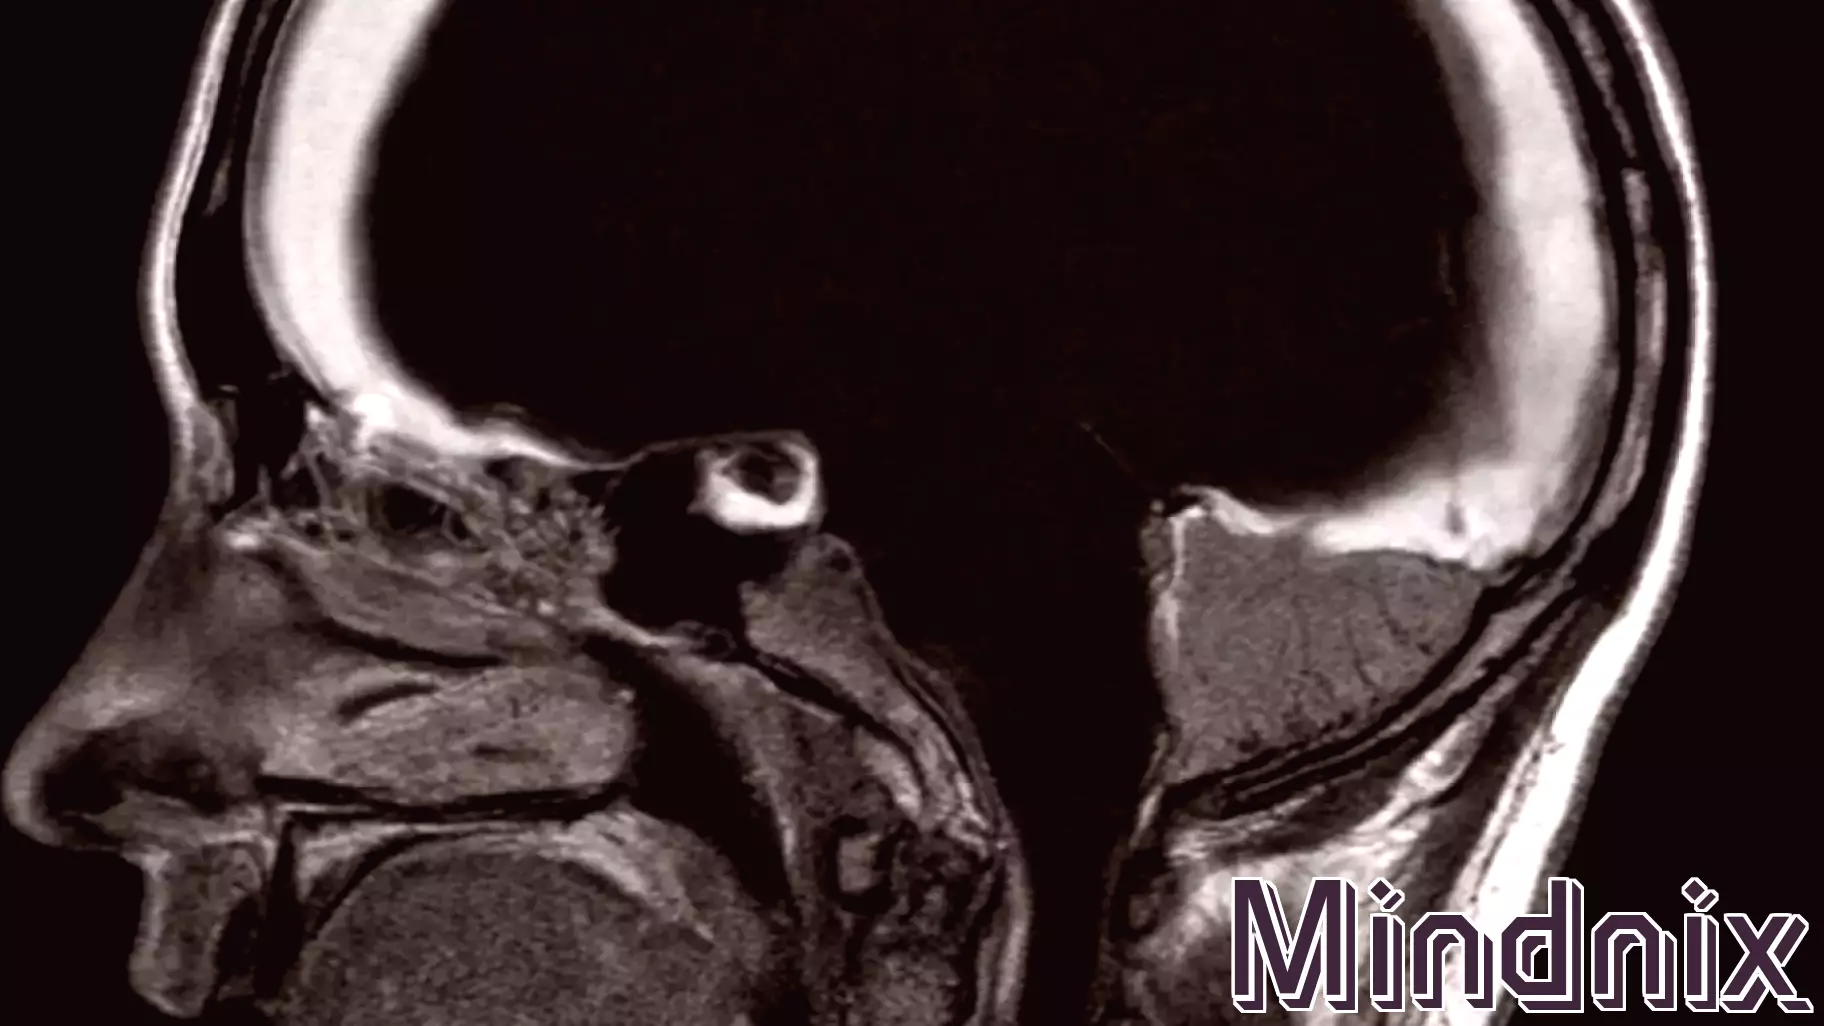

In a remarkable case, a French civil servant demonstrated normal cognitive functioning despite having 90 percent of his brain missing. This astonishing phenomenon raises intriguing questions about the nature of intelligence and the brain's role in our overall cognitive abilities.

Recent research suggests that intelligence may not be confined solely to the brain; rather, it could be distributed throughout the entire body. This challenges long-held beliefs about the brain as the singular control center for our thoughts, emotions, and actions.

Neuroscientists are now exploring the idea that other systems within the body, including the nervous system and even the gut, may play significant roles in our cognitive processes. The findings could lead to a paradigm shift in understanding how we define intelligence and how we approach neurological health.

As we delve deeper into the complexities of human cognition, this case serves as a powerful reminder of the brain's incredible adaptability and the potential for intelligence to manifest in unexpected ways.